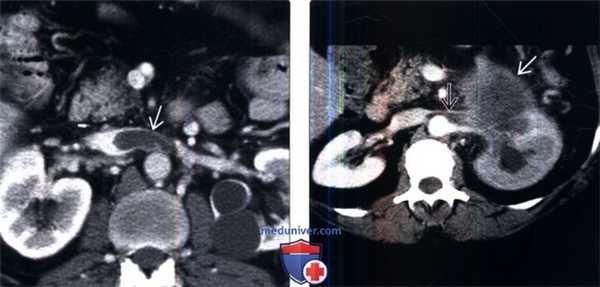

(Левый) У этого пациента имеется хроническая обструкция почки (выполнено стентирование) и инфекционный процесс вследствие опухоли мочевого пузыря. На аксиальном КТ срезе с контрастированием визуализируется цилиндрический низкоинтенсивный дефект наполнения в левой почечной вене, практически с отсутствующим кровотоком по периферии тромба.

(Правый) На фронтальном реформатированном КТ срезе у другого пациента с нефротическим синдромом визуализируется распространенный тромбоз левой почечной вены с переходом на НПВ. Этот пациент впоследствии перенес тромбоэмболию мелких ветвей легочной артерии.

(Слева) МРТ, постконтрастное Т1-ВИ, аксиальная проекция: у мужчины 59 лет, в анамнезе у которого имеется образование правой почки, выявлен обширный тромбоз правой почечной вены с продолжением в НПВ и поясничную ветвь. Обратите внимание на увеличение правой почки и отсроченную нефрограмму вследствие венозного тромбоза.

(Справа) МРТ, Т2-ВИ, аксиальная проекция: у этого же пациента выявлен измененный Т2-сигнал от правой почки вследствие венозного тромбоза и перегрузки. При патоморфологическом исследовании был подтвержден светлоклеточный ПКР.

(Слева) КТ с контрастированием, аксиальная проекция: у женщины 60 лет выявлено контрастируемое образование в средней части правой почки с опухолевым тромбозом правой почечной вены. Обратите внимание на значительное расширение почечной вены.

(Слева) КТ с контрастированием, аксиальная проекция: у женщины 46 лет с жалобами на боли в животе неясной этиологии и недостатком протеина 5 в анамнезе выявлен тромб в нижней полой и левой почечной венах.

(Справа) КТ с контрастированием, аксиальная проекция: у пациента с жалобами на потерю веса и боль в боку выявлено образование хвоста поджелудочной железы, охватывающее левую почечную вену, что в результате привело к ее тромбозу . Обратите внимание на задержку нефрограммы и гидронефроз.